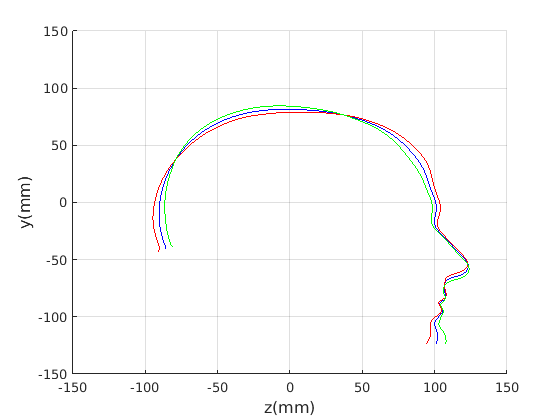

Figure 16 shows examples of the robust ellipse fit for four head profiles. The centre of the ellipse is used in a pose normalisation procedure where the ellipse centre is used as the origin of the profile and the angle from the ellipse centre to the nasion is fixed at -10 degrees. We call this Ellipse Centre - Nasion (ECN) pose normalisation and later compare this to GPA. The major and minor axes of the extracted ellipses are plotted as red and green lines respectively in Fig. 16.

|

Figure 17 shows all 100 profiles overlaid with the same alignment scheme. The median value of major ellipse axis and the ellipse centre-nasion angle differ by 3.6 degrees, so that when the nasion angle is fixed at -10 degrees, the median ellipse angle is -6.4 degrees (cf. -7.4 degrees with manual landmarking of the nasion). We noted regularity in the orientation of the fitted ellipse as is indicated by the clustering of the major (red) and minor (green) axes in Fig. 17 and the histogram of ellipse orientations in Fig. 18. For most people, the major axis of the ellipse is closely aligned with the y-axis (upright), and titled slightly forwards. A minority of heads (9%) in the training sample have their major ellipse axes closer to the vertical (these relatively tall and short heads are known as brachycephalic.) Ellipse axis clustering (relative to the fixed ellipse centre-nasion line) does not appear to be sharply defined. This is because many crania are close to circular in cross-section, making the orientation of these angles sensitive to small changes in shape from one person to the next. Note also the variation at the back of the head due to a variety of hair styles, some of which protrude from under the cap. We limit the region over which we model the cranial shape in order to crop this unwanted data out.